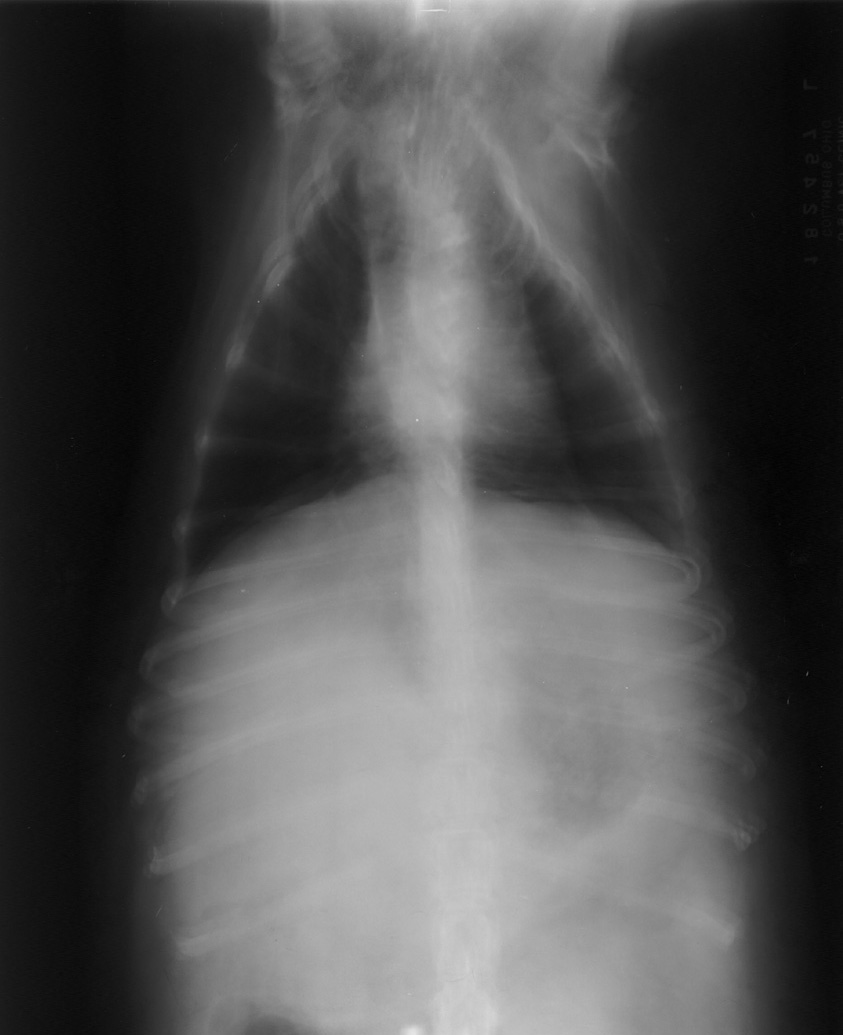

Double Exposures